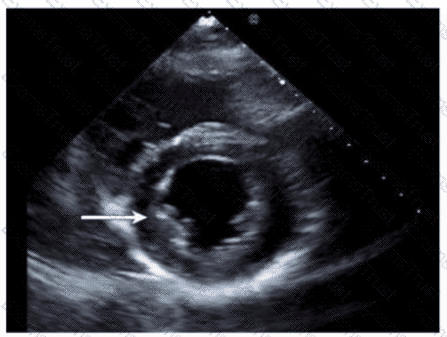

Which type of defect can be seen in this video clip?